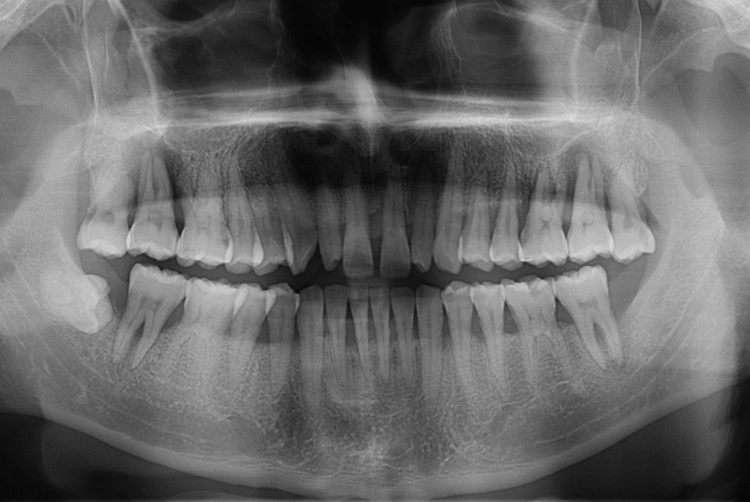

[임플란트] 어금니 임플란트

치료전 : 2017-07-10